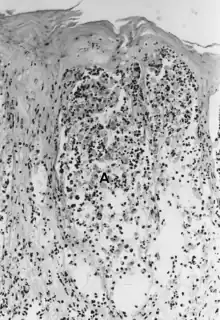

| Foot-and-mouth disease - acantholysis in a sample of a skin vesicle: Necrosis of the stratum spinosum can be observed, and keratinocytes floating in the vesicular fluid (spongiosa). | |

Acantholysis is the loss of intercellular connections, such as desmosomes, resulting in loss of cohesion between keratinocytes,[1] seen in diseases such as pemphigus vulgaris.[2] It is absent in bullous pemphigoid, making it useful for differential diagnosis.

This histological feature is also seen in herpes simplex infections (HSV 1 and 2) and varicella zoster infections (chicken pox and shingles).